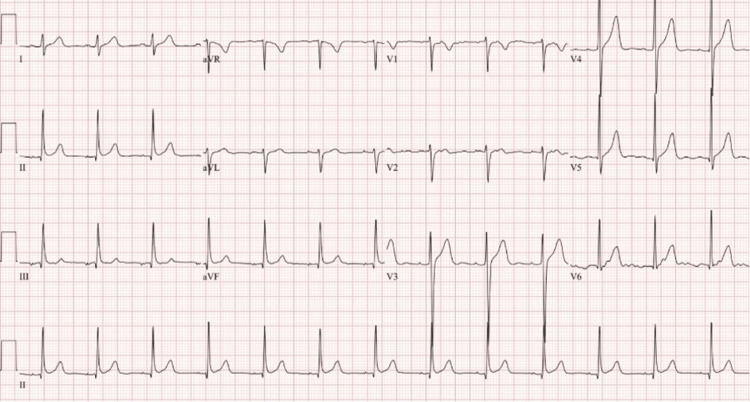

In addition, an EKG and CT scan of the head were done to rule out any organic causes for the patient’s presentation. The EKG is shown in Figure 1, normal sinus rhythm with a ventricular rate of 79 beats per minute with a QTc of 410 milliseconds, and no signs of arrhythmias or myocardial infarctions. The CT of the head without contrast demonstrated in Figure 2 shows no signs of an acute infarct or intracranial hemorrhage, with mild cerebral atrophy.